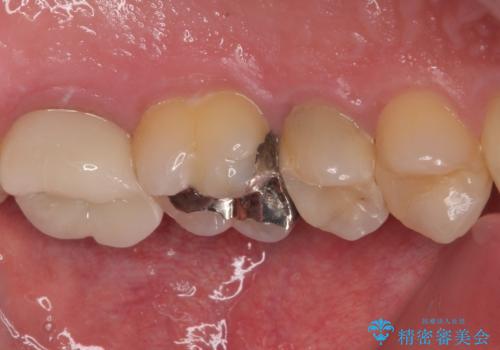

拡大鏡視野下で、セラミックの詰め物、虫歯の除去を行い、オールセラミッククラウンに適した形に整えました。

歯と歯茎の間に圧排糸と言われる糸を入れてシリコーン印象材にて型どりをしました。